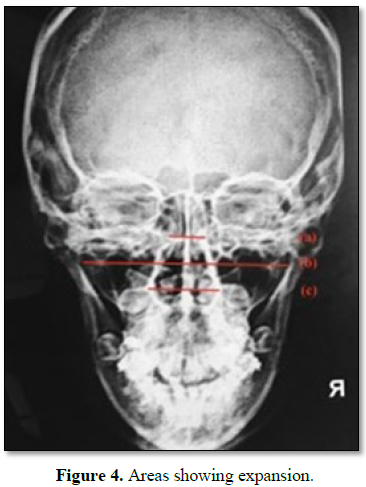

Post expansion transverse measurements of frontonasal area, zygomatic arch and nasal cavity should be recorded and compared to the pre-treatment values to evaluate and compare the skeletal changes. Maximum expansion is usually seen in the nasal cavity [30] followed by zygomatic arch and frontonasal area (Figure 4).

While zygomatic arch expanded to a lesser extent, expansion of nasal cavity was much more evident, and thus can result in improvement of nasal breathing owing to increased air flow. Thus, by effectively increasing the nasal cavity volume, treatment with a MARPE appliance can improve the constricted airway, thus aiding in long-term stability [18,67,68].